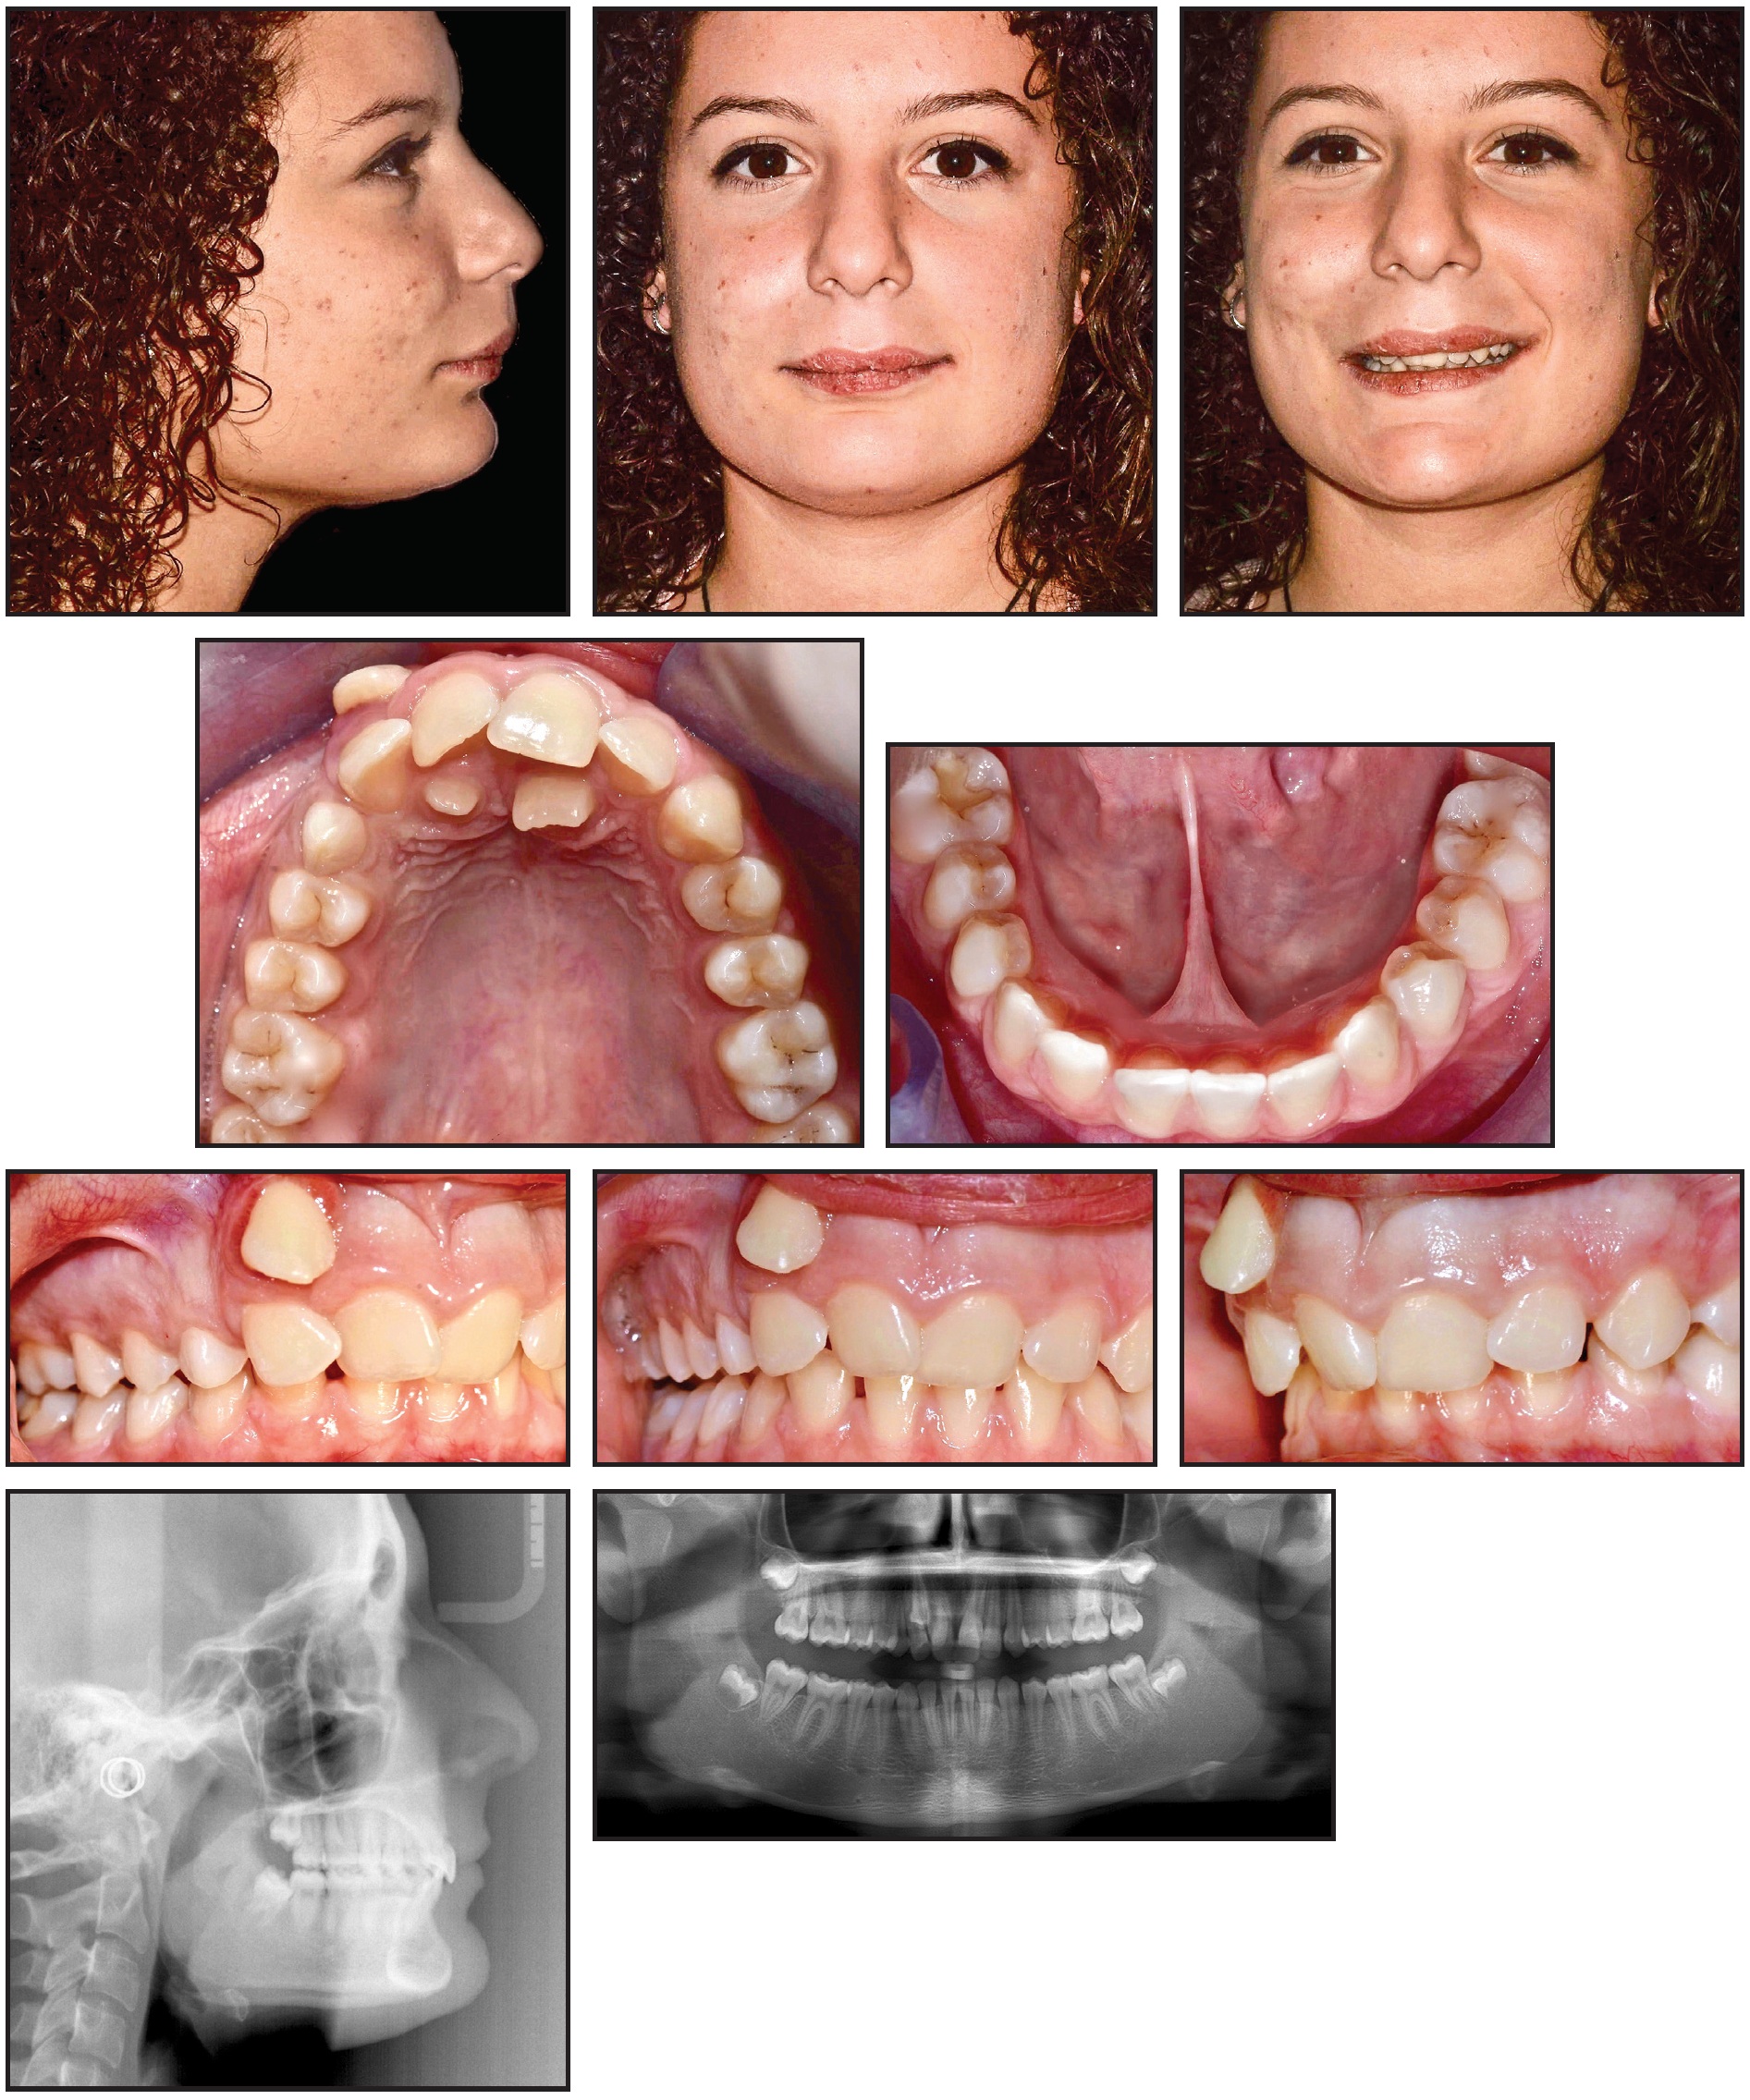

A 13-year-old female in the permanent dentition presented with a persistent upper right deciduous canine and an ectopically impacted permanent canine (Fig. 2).

Fig. 2 13-year-old female patient with Class II molar and canine relationships and ectopic upper right canine completely transposed with upper right lateral incisor before treatment.

Clinical examination found Class II molar and canine relationships and a severe deep bite, with an accentuated curve of Spee. The upper right permanent canine was ectopic and highly displaced in the vestibule, in complete transposition with the right lateral incisor. The patient had a symmetrical face, a straight profile, a normal nasolabial angle, an accentuated labiomental groove, a prominent symphysis, and a short lingual frenulum. The smile arc was narrow, with an irregular curvature but no excessive gingival exposure, and lip competence was adequate at rest. Because of the canine transposition, the upper midline was deviated 5mm to the right and the lower midline 3mm to the left.

The panoramic radiograph confirmed a complete canine and lateral incisor transposition, the persistence of the upper right deciduous canine, and the presence of two anomalous supernumerary teeth in a palatal position. All four third molars were in a mid-developmental stage. Cephalometric analysis indicated a hypodivergent skeletal Class II malocclusion (Wits appraisal = +3.2) with a normal mandibular structure (Table 1).